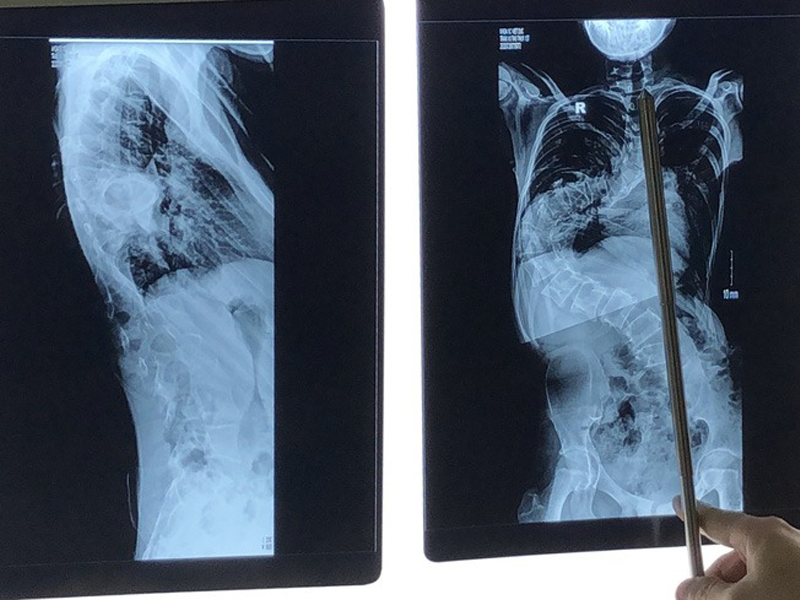

Hình ảnh trên phim chụp cho thấy cột sống bệnh nhân uốn lượn như hình chữ S. Các đốt sống bình thường xếp chồng lên nhau thành một đường thẳng đứng thì nay xếp thành đường cong, nhiều đoạn gần như nằm ngang. Đốt sống nằm sát vào thành ngực thay vì nằm giữa cơ thể.

Hình ảnh cột sống uốn cong hình chữ S của bệnh nhi 13 tuổi